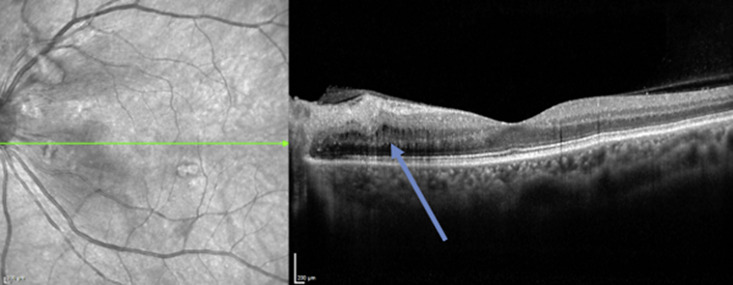

Case presentation: We narrate all reported cases of TA in patients with MS and report the case of a 57-year-old woman with MS with suspected bilateral optic neuritis and typical contrast-medium enhancement in both optic nerves. Because of normal visual acuity on both eyes, malignant hypertension, and fundoscopic findings indicative of hypertensive retinopathy, we diagnosed hypertensive retinopathy with secondary contrast-medium enhancement of the optic nerves. We established antihypertensive medication and searched for secondary causes of hypertension and highly elevated erythrocyte sedimentation rate, which led to the finding of large vessel wall inflammation and the diagnosis of TA.